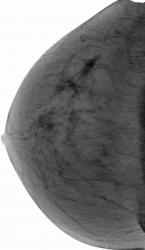

СЛУЧАЙ РЫБАКОВОЙ Л. А. "Инфильтрирующий рак правой молочной железы".

"Инфильтрирующий рак правой молочной железы".